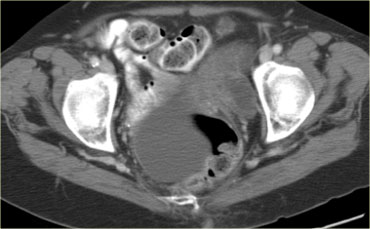

Trường hợp tiếp theo là siêu âm qua thành bụng cho thấy một khối nang đa thùy bên trái.

Hình ảnh này gợi ý u nang tân sinh buồng trứng nhưng không xác định được buồng trứng.

CT trên cùng bệnh nhân cho thấy một khối nang đa thùy tiếp giáp bàng quang, có liên quan đến tĩnh mạch buồng trứng trái (mũi tên).

Có các vách ngăn dày và thành dày không đều.

Dựa trên hình ảnh CT này, không thể phân biệt giữa tổn thương buồng trứng lành tính như u nang tuyến xơ và tổn thương buồng trứng ác tính.

Tổn thương được phẫu thuật cắt bỏ và kết quả giải phẫu bệnh xác định là u nang tuyến xơ.